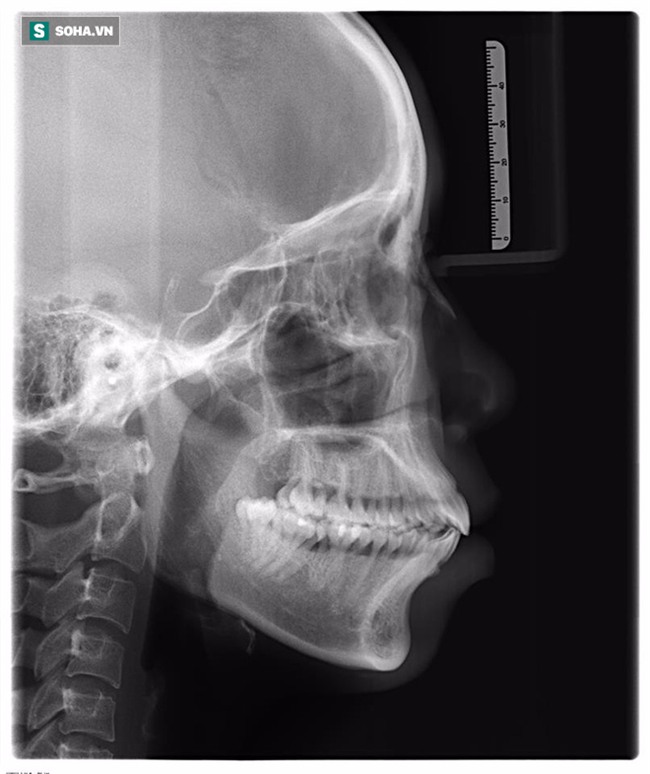

Em bắt đầu phẫu thuật cách đây hơn 2 tháng. Em sợ đau chứ, nhưng lúc ấy lòng quyết tâm lớn hơn tất cả. Đầu tiên, em phẫu thuật hàm trên dưới. Khi đó đau lắm, phải ăn cháo, hút sữa gần 2 tuần liền. May mắn có cô em gái ở chung chăm sóc. Sợ bố mẹ ở quê lo lắng nên em không báo ngày bắt đầu làm.

Em đau đớn lắm, mỗi lúc như vậy lại nghĩ: 'Sắp đẹp rồi, cố lên nào, sắp đẹp rồi' để quên đi. Sau đó, em nâng mũi và trị cau mày, tạm biệt hẳn biệt danh 'mũi lợn' ngày xưa. Để đẹp lên, em đã chịu đựng tất cả".